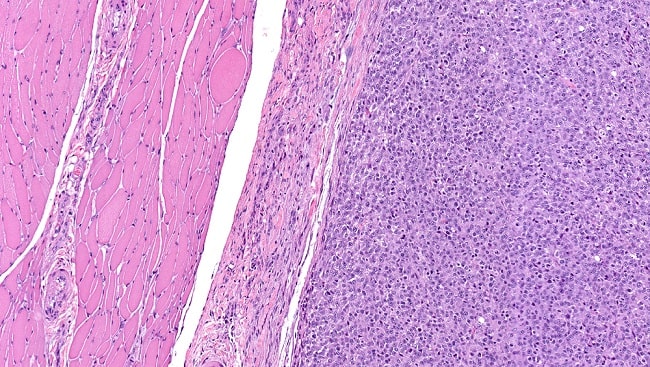

Berdasarkan gambaran histopatologinya, yang penting untuk menentukkan prognosis pasien, terdapat beberapa subtipe dari rhabdomyosarcoma, antara lain:

Embryonal rhabdomyosarcoma,

- Alveolar rhabdomyosarcoma,

- Pleomorphic rhabdomyosarcoma,

Botryoid and spindle cell (leiomyomatous) rhabdomyosarcoma[3,4]

Sementara itu, World Health Organization (WHO) membedakan rhabdomyosarcoma menjadi empat kategori, yaitu embryonal rhabdomyosarcoma (60%), alveolar rhabdomyosarcoma (20%), pleomorphic rhabdomyosarcoma (10%), dan spindle/sclerosing rhabdomysosarcoma (10%). Rhabdomyosarcoma dapat menyerang semua bagian tubuh yang memiliki otot termasuk kepala dan leher (45%), dada dan perut (40%), ekstremitas (15%). Adapun 25%-30% dari rhabdomyosarcoma pada kepala dan leher berasal dari orbita.[1,5]